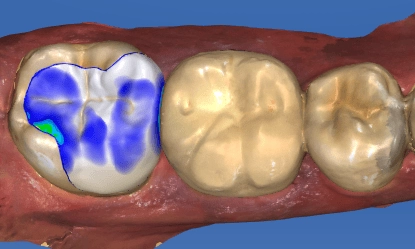

3D電腦製作

- 進行CEREC 3D齒雕口內掃描,經由電腦設計、繪圖及研磨。